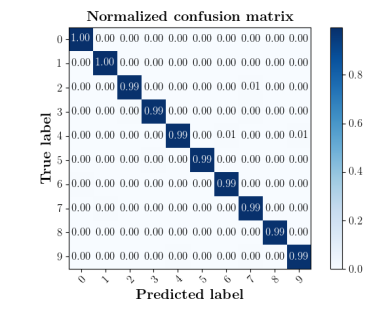

We further compare the performance of MIDNet with and without unlabeled data on the target domain. Here, the with unlabeled data setting utilizes the training data containing labeled data and unlabeled data, while the without unlabeled data setting only uses the labeled data. The confusion matrices in Fig. 8(a) show the effectiveness of unlabeled data in the proposed method, for example, the classification accuracy of in MIDNet (e.g., 4CH and Lips) improves when integrating unlabeled data.

We further compare the performance of MIDNet in a semi-supervised setting and a fully-supervised setting. Here, the semi-supervised setting utilizes the training data containing labeled data and unlabeled data, while the fully supervised setting only uses the labeled data. The confusion matrix in Fig. 14 shows the effectiveness of unlabeled data in our proposed method, for example, the classification accuracy of greatly improves when integrating unlabeled data (semi-supervised).